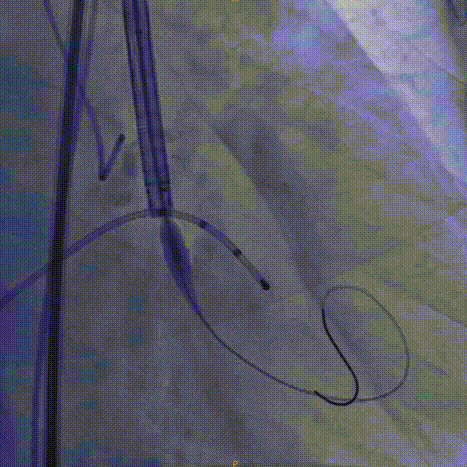

术中影像:

Venus26号瓣膜释放:前三分之一慢放精准定位,中三分之一快放使瓣膜快速进入工作状态。

Venus26号瓣膜释放:位置良好,轻度反流,遂完全释放后采取后扩。

后扩后瓣膜最终形态。